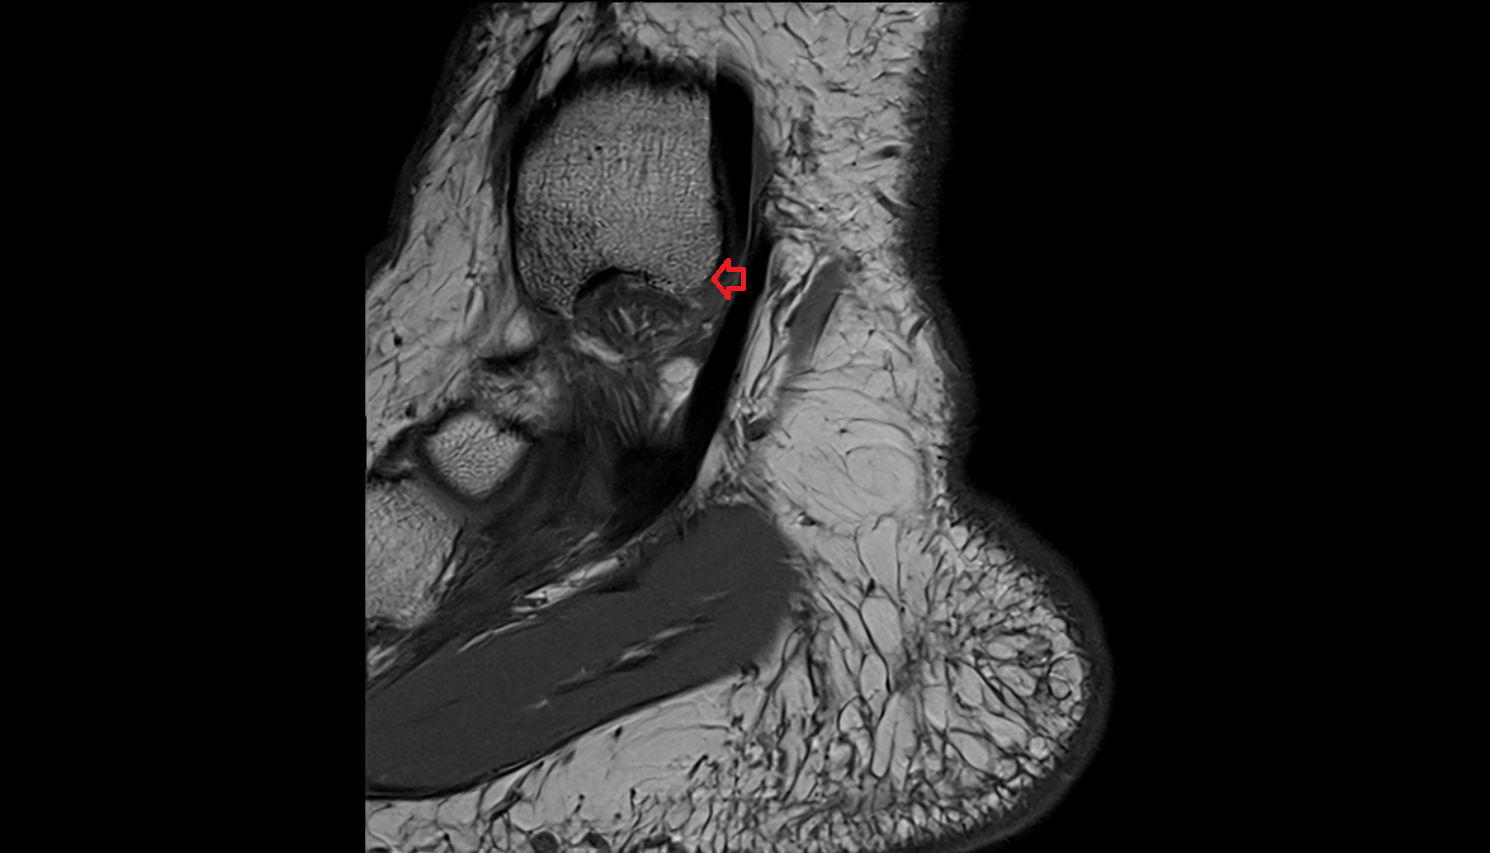

- Talus

- Head of talus

- Body of talus

- Neck of talus

- Calcaneus

- Sustentaculum tali

- Medial malleolus

- Lateral malleolus

- Ankle joint

- Achilles tendon

- Anterior talofibular ligament

- Posterior talofibular ligament

- Deltoid ligament complex

- Talocalcaneal interosseous ligament

- Kager fat pad (pre-Achilles fat pad)